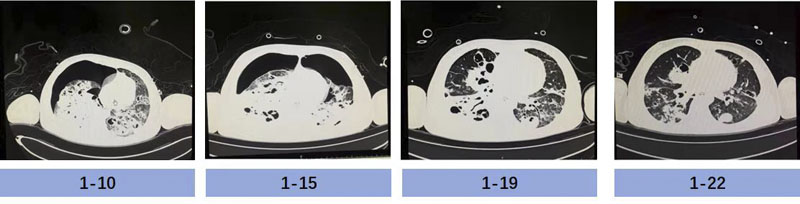

成功撤离ECMO,只是“生命闯关”的第一步,如何控制感染、恢复肺功能、脱离呼吸机支持、避免院内感染及获得性肌无力,是医护人员面对的又一个难题。根据基因测序及培养结果回报,患儿血液及肺泡灌洗液标本中均检出大量金黄色葡萄球菌(基因序列数高达一百多万条)及流感嗜血杆菌(基因序列数高达二十多万条),两者叠加,破坏力巨大;患儿肺部影像学提示:双肺大面积实变、渗出及空洞,极易引发自发性气胸。

胡振杰主任临床经验丰富,在病原学结果回报之前就判断患儿金黄色葡萄球菌感染可能性大,结合迅速发展的多脏器功能衰竭症状,第一时间应用了广谱抗生素(美罗培南联合利奈唑胺)抗感染治疗。随着药敏结果回报,金黄色葡萄球菌为敏感菌株,指南推荐甲氧西林敏感的金葡菌(MSSA)肺炎首选抗葡萄球菌青霉素类与一代头孢,而甲氧西林耐药的金葡菌(MRSA)肺炎首选万古霉素、利奈唑胺。考虑到患儿并不是单纯的MSSA肺炎,合并血流感染及多脏器功能衰竭,并且对头孢类药物过敏,抗生素选择应精准且符合实际,斟酌再三,胡振杰主任毅然选择了单纯应用哌拉西林他唑巴坦抗感染治疗,一定程度上避免了广谱抗生素导致的耐药菌发生。为更好地改善患儿肺部通气不均一性,医护人员协助患者行俯卧位通气治疗,密切监测肺部体征和影像学评估,第一时间发现气胸并紧急请胸外科医师为患儿行胸腔闭式引流术,反复调整引流管位置,给予负压吸引,进一步促进肺泡扩张。